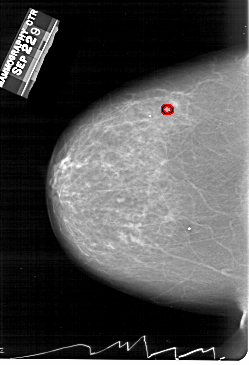

A_1260_1.LEFT_CC

LEFT_CC LINES 6556 PIXELS_PER_LINE 4471 BITS_PER_PIXEL 12 RESOLUTION 43.5 OVERLAY

FILE: A_1260_1.LEFT_CC.OVERLAY

TOTAL_ABNORMALITIES 1

ABNORMALITY 1

LESION_TYPE MASS SHAPE ARCHITECTURAL_DISTORTION MARGINS ILL_DEFINED

ASSESSMENT 4

SUBTLETY 2

PATHOLOGY MALIGNANT

TOTAL_OUTLINES 1

BOUNDARY